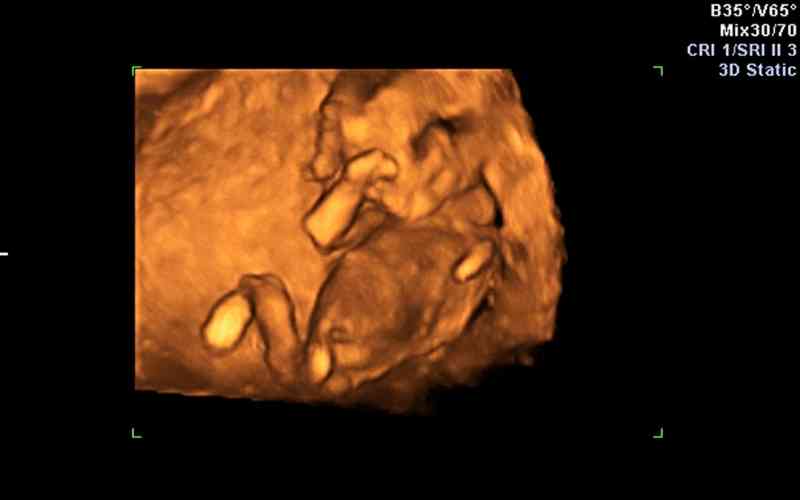

Đến cuối tam cá nguyệt thứ hai, thai nhi 28 tuần tuổi có thể đạt 1,1 kg, chiều dài có thể lên đến 40 cm. Mẹ có thể cảm nhận được một số cử động của thai nhi trong bụng như đá, xoay người, di chuyển,...Trong giai đoạn này, các cơ quan, bộ phận của thai nhi đã phát triển đầy đủ, não bộ cũng phát triển với tốc độ rất nhanh.

Khi siêu âm thai, ba mẹ có thể quan sát được rõ hình thái, cử chỉ của thai nhi. Lông mi, móng chân, móng tay đã phát triển. Một lớp lông tơ mịn màng cũng dần bao phủ trên thân hình của bé, đặc biệt là tóc phát triển nhanh. Bé thường ngủ và thức dậy theo chu kỳ, mí mắt có thể đóng mở lại.